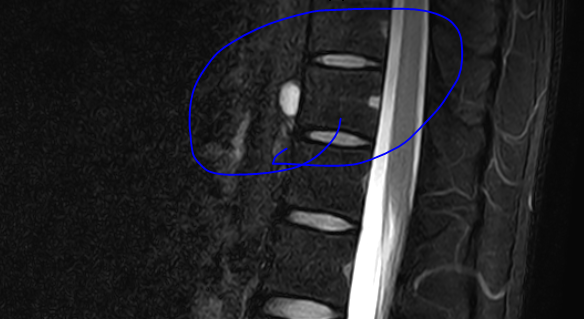

안녕하세요 이번에 MRI를 촬영했는데 척추 앞부분에 이상한 Cyst?같은게 있어서 혹시 아시는분이 있으신지 여쭤보고자 질문드립니다.

• 1번 째 사진